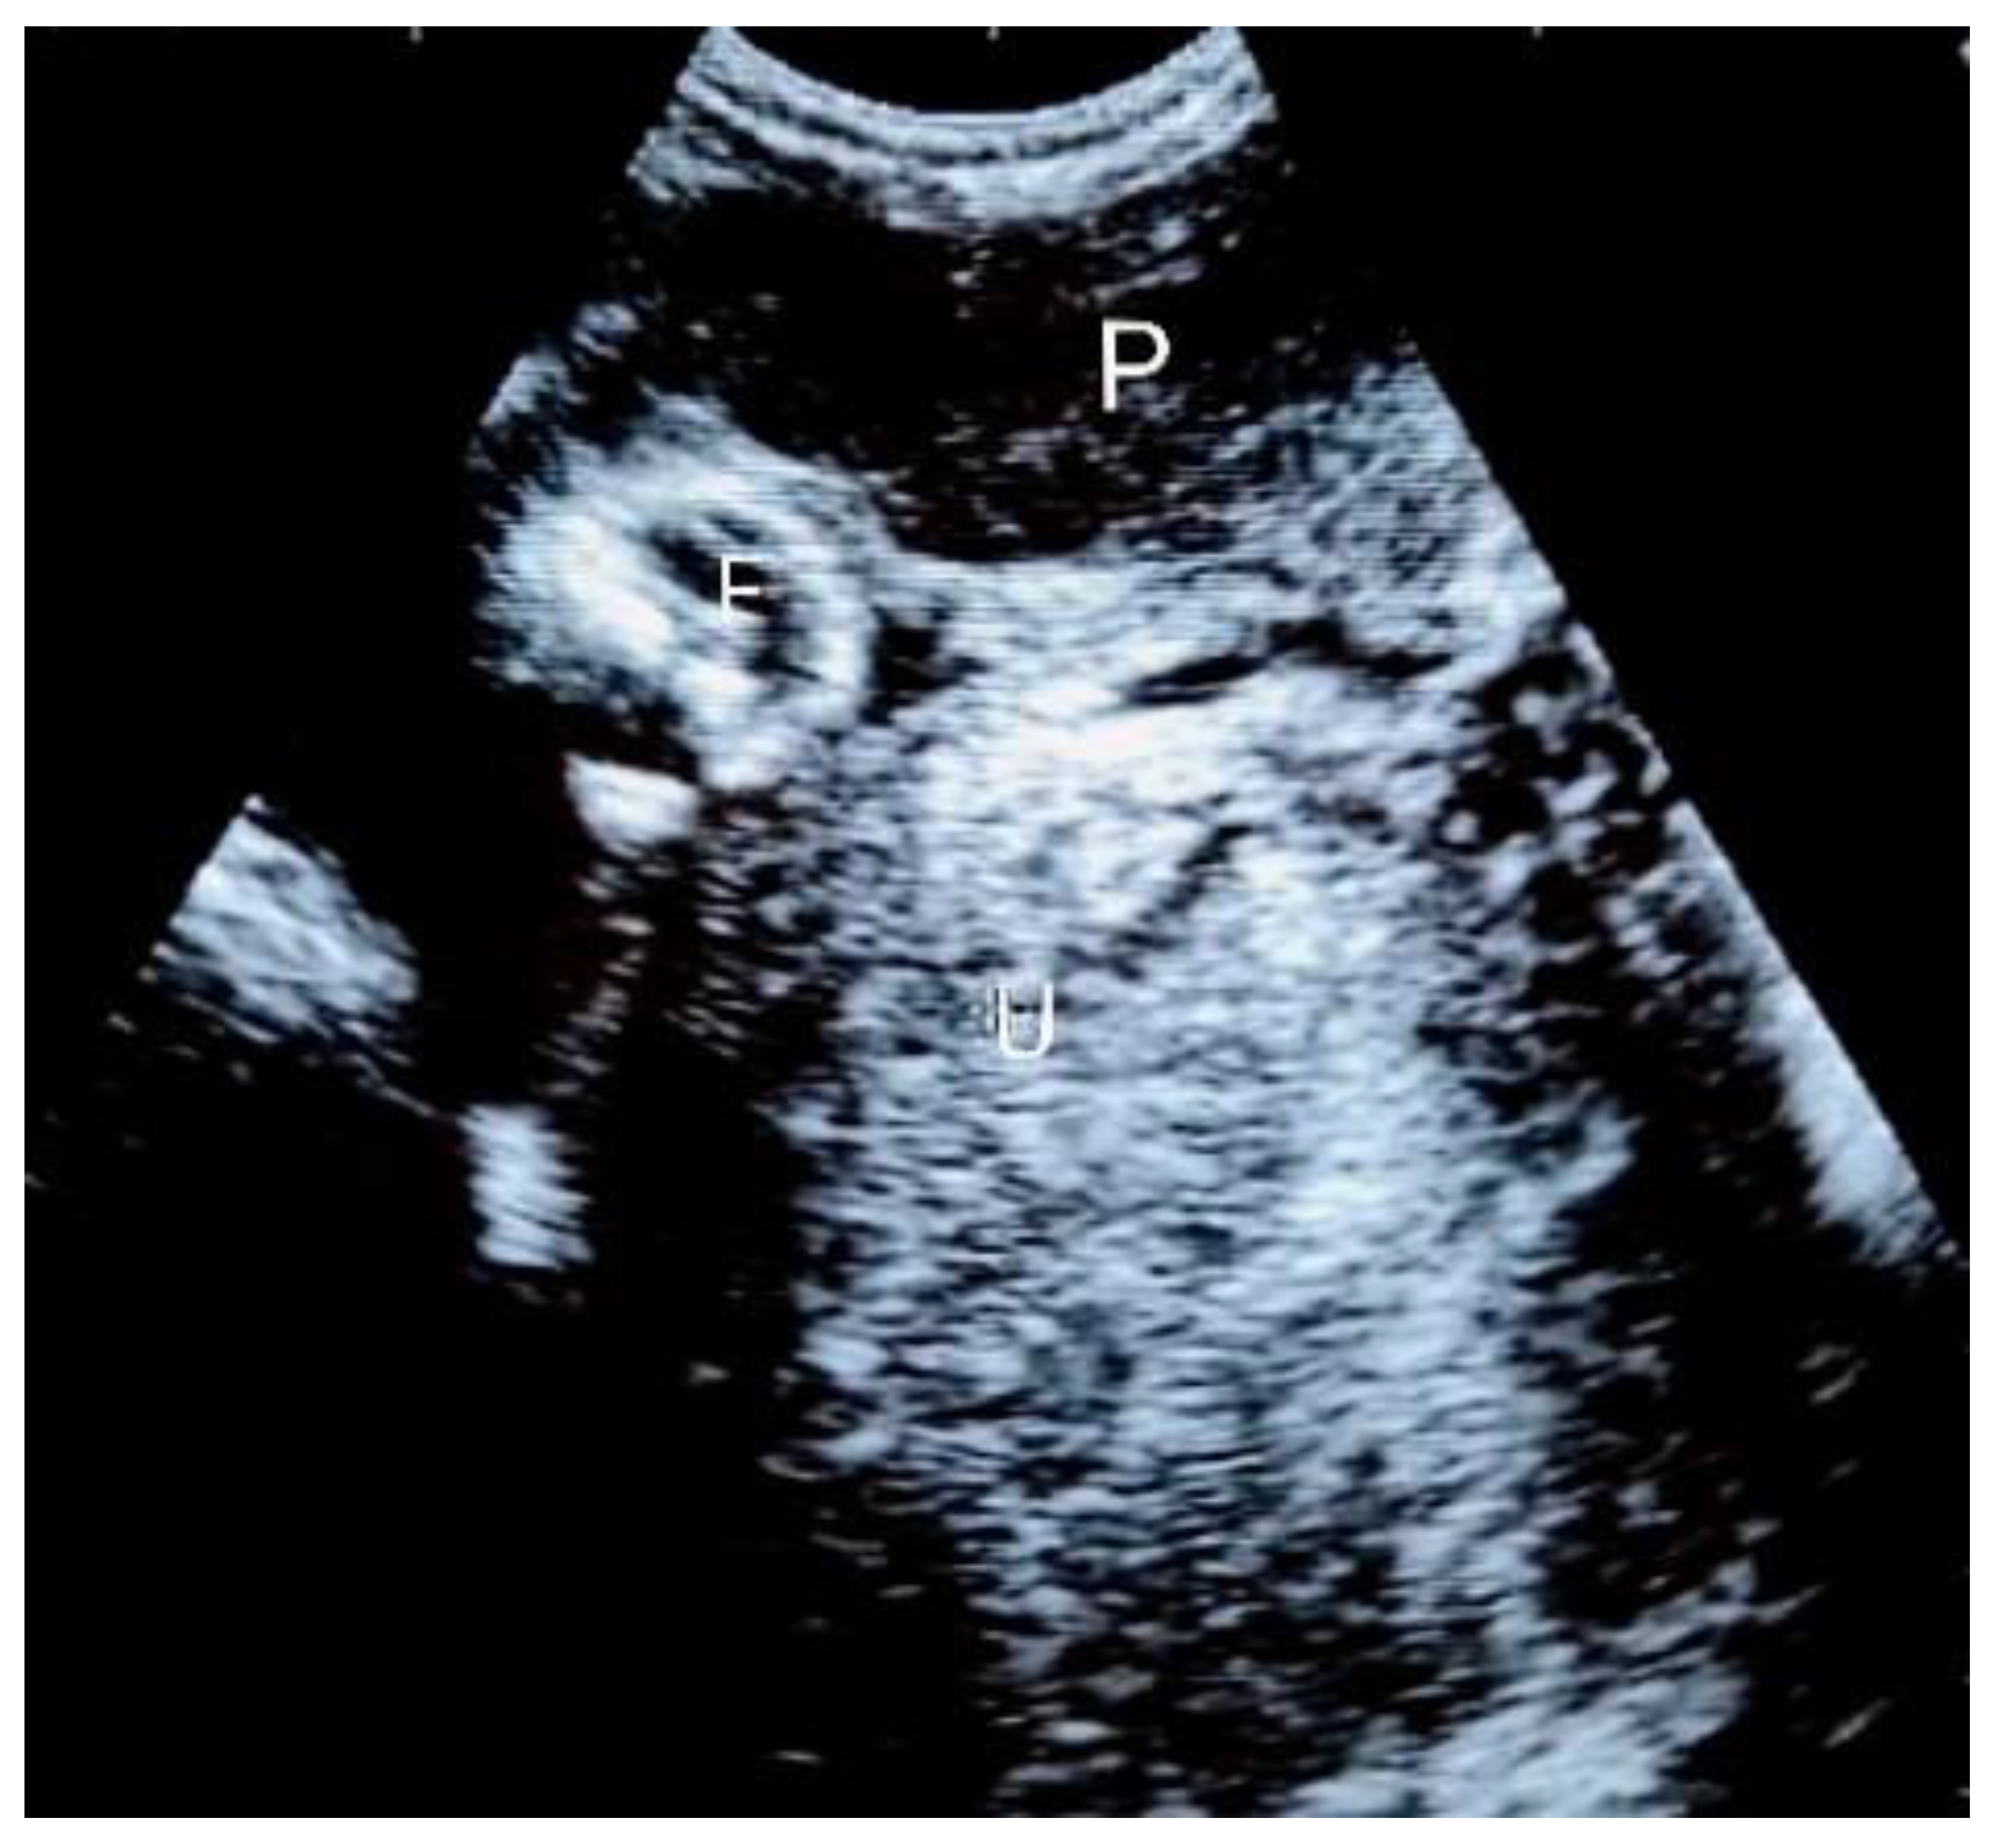

Figure 2.

Third trimester abdominal ultrasound scan (left-lateral view) showing the fetal limbs, placenta, amniotic fluid, and the empty uterus. P = placenta; F = fetal limbs; U = uterus.

Considering the previous salpingectomy and subsequent fertility implications, the patient outrightly refused both surgery and hospital admission, even after the proposal to only be hospitalized and remain monitored without immediate intervention. Analgesics and hematinics were then prescribed and a short-term outpatient follow-up was then advised. She defaulted on antenatal follow-up visits, and she avoided responding to repeated attempts of the medical staff to contact her. She only came to the hospital at 26 weeks of gestation. An ultrasound scan was then repeated (Figure 2). The fetus was still vital and growing within the normal range, with adequate amniotic fluid and normal umbilical flow at the Doppler ultrasound assessment. She was then admitted for close monitoring and expectant management. Fetal lung maturation was induced by maternal intramuscular injection of corticosteroids at 28 weeks of gestational age, in order to reduce the risk of severe neonatal respiratory distress syndrome.